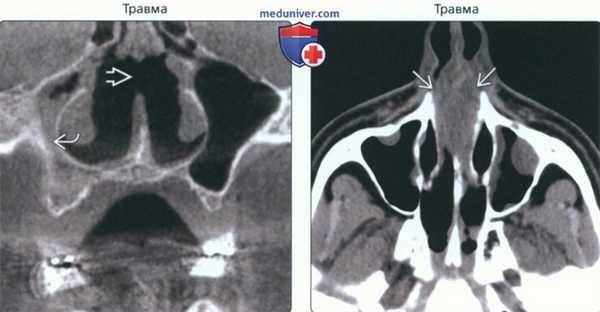

(Слева) На корональной КЛКТ определяется дугообразное отклонение нижних отделов носовой перегородки вправо. Определяется сужение нижнего носового хода вследствие утолщения нижней носовой раковины.

(Справа) На корональной КТ в костном окне визуализируется крупный экзостоз носовой перегородки с широким основанием, выдающийся в средний носовой ход. Обратите внимание на сужение просвета.

(Слева) На корональной КЛКТ определяется перфорация носовой перегородки после хирургического лечения по поводу хронического синусита. Определяются также признаки правостороннего гайморита.

(Справа) На аксиальной КТ без КУ в хрящевой и костной части носовой перегородки визуализируется экспансивный очаг, который клинически был расценен как гематома, хотя и не выглядит гиперденсным на КТ. Гематома обусловлена травмой этой области.